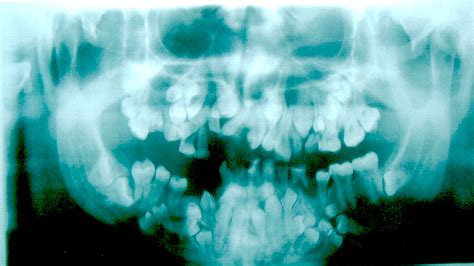

Radiografía que muestra características de la displasia cleidocraneal.

Este trastorno se caracteriza por tratarse de una rara alteración congénita del esqueleto, asociado a hipoplasia o aplasia clavicular, retardo en el cierre de las fontanelas craneales, con morfología braquiocefálica, retraso de la exfoliación de la dentición temporal, erupción retardada de dientes permanentes, presencia de varios supernumerarios y alteraciones morfológicas del maxilar y mandíbula (figs.